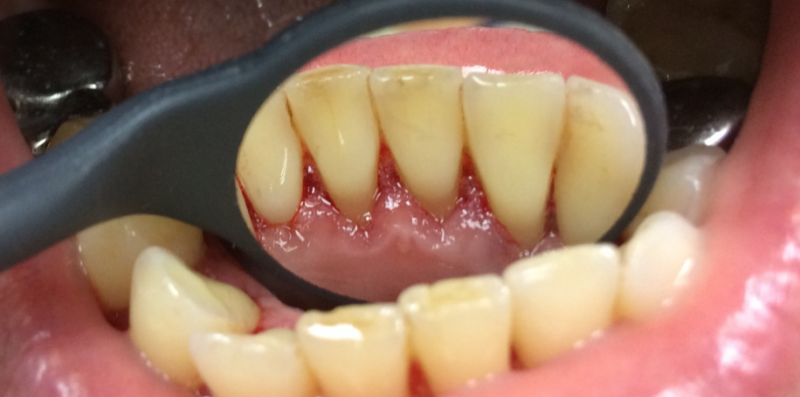

Профессиональная гигиена особенно важна при ортодонтическом лечении, ведь в повседневной жизни, дома, очень сложно поддерживать должный уровень гигиены полости рта! Даже если вы используете ирригатор и специальные ёршики! В нашей рубрике «до/после» вы видите то, что может быть с зубами при лечении брекетами, если не проводить своевременную чистку у врача-стоматолога. Марухно Дарья Александровна провела профессиональную чистку в несколько этапов, чтобы вернуть пациентке белизну ее собственных зубов! Брекет-система была поставлена не в нашей клинике, и почему пациентка не обратилась за профессиональной помощью раньше-вопрос) Но в данном случае, главное – итог! Кровоточивость после даже обычной чистки в такой клинической ситуации – естественный результат. Ведь обильный зубной налёт и зубной камень вызывают воспаление дёсен в виде гингивита, а порой даже пародонтита.

Доктор: Марухно Дарья Александровна